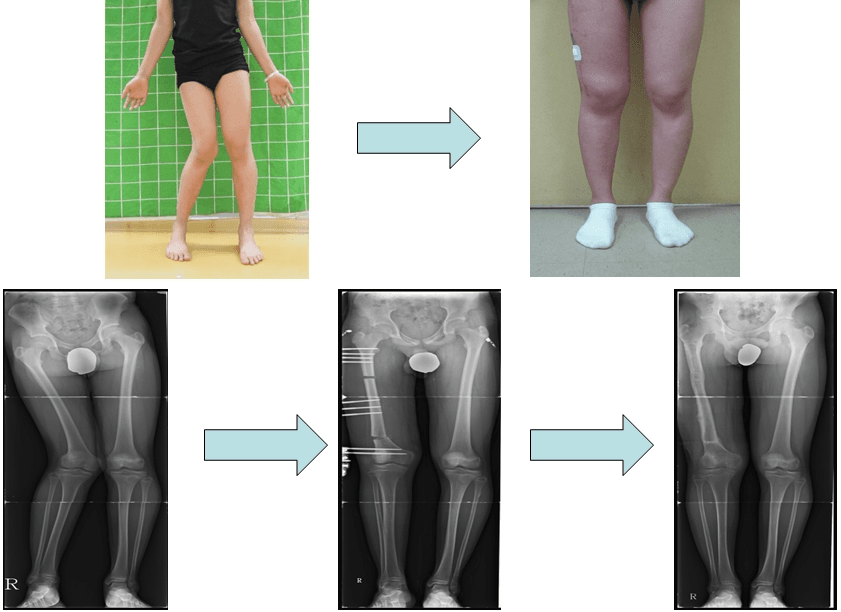

밖으로 휜 다리의 교정